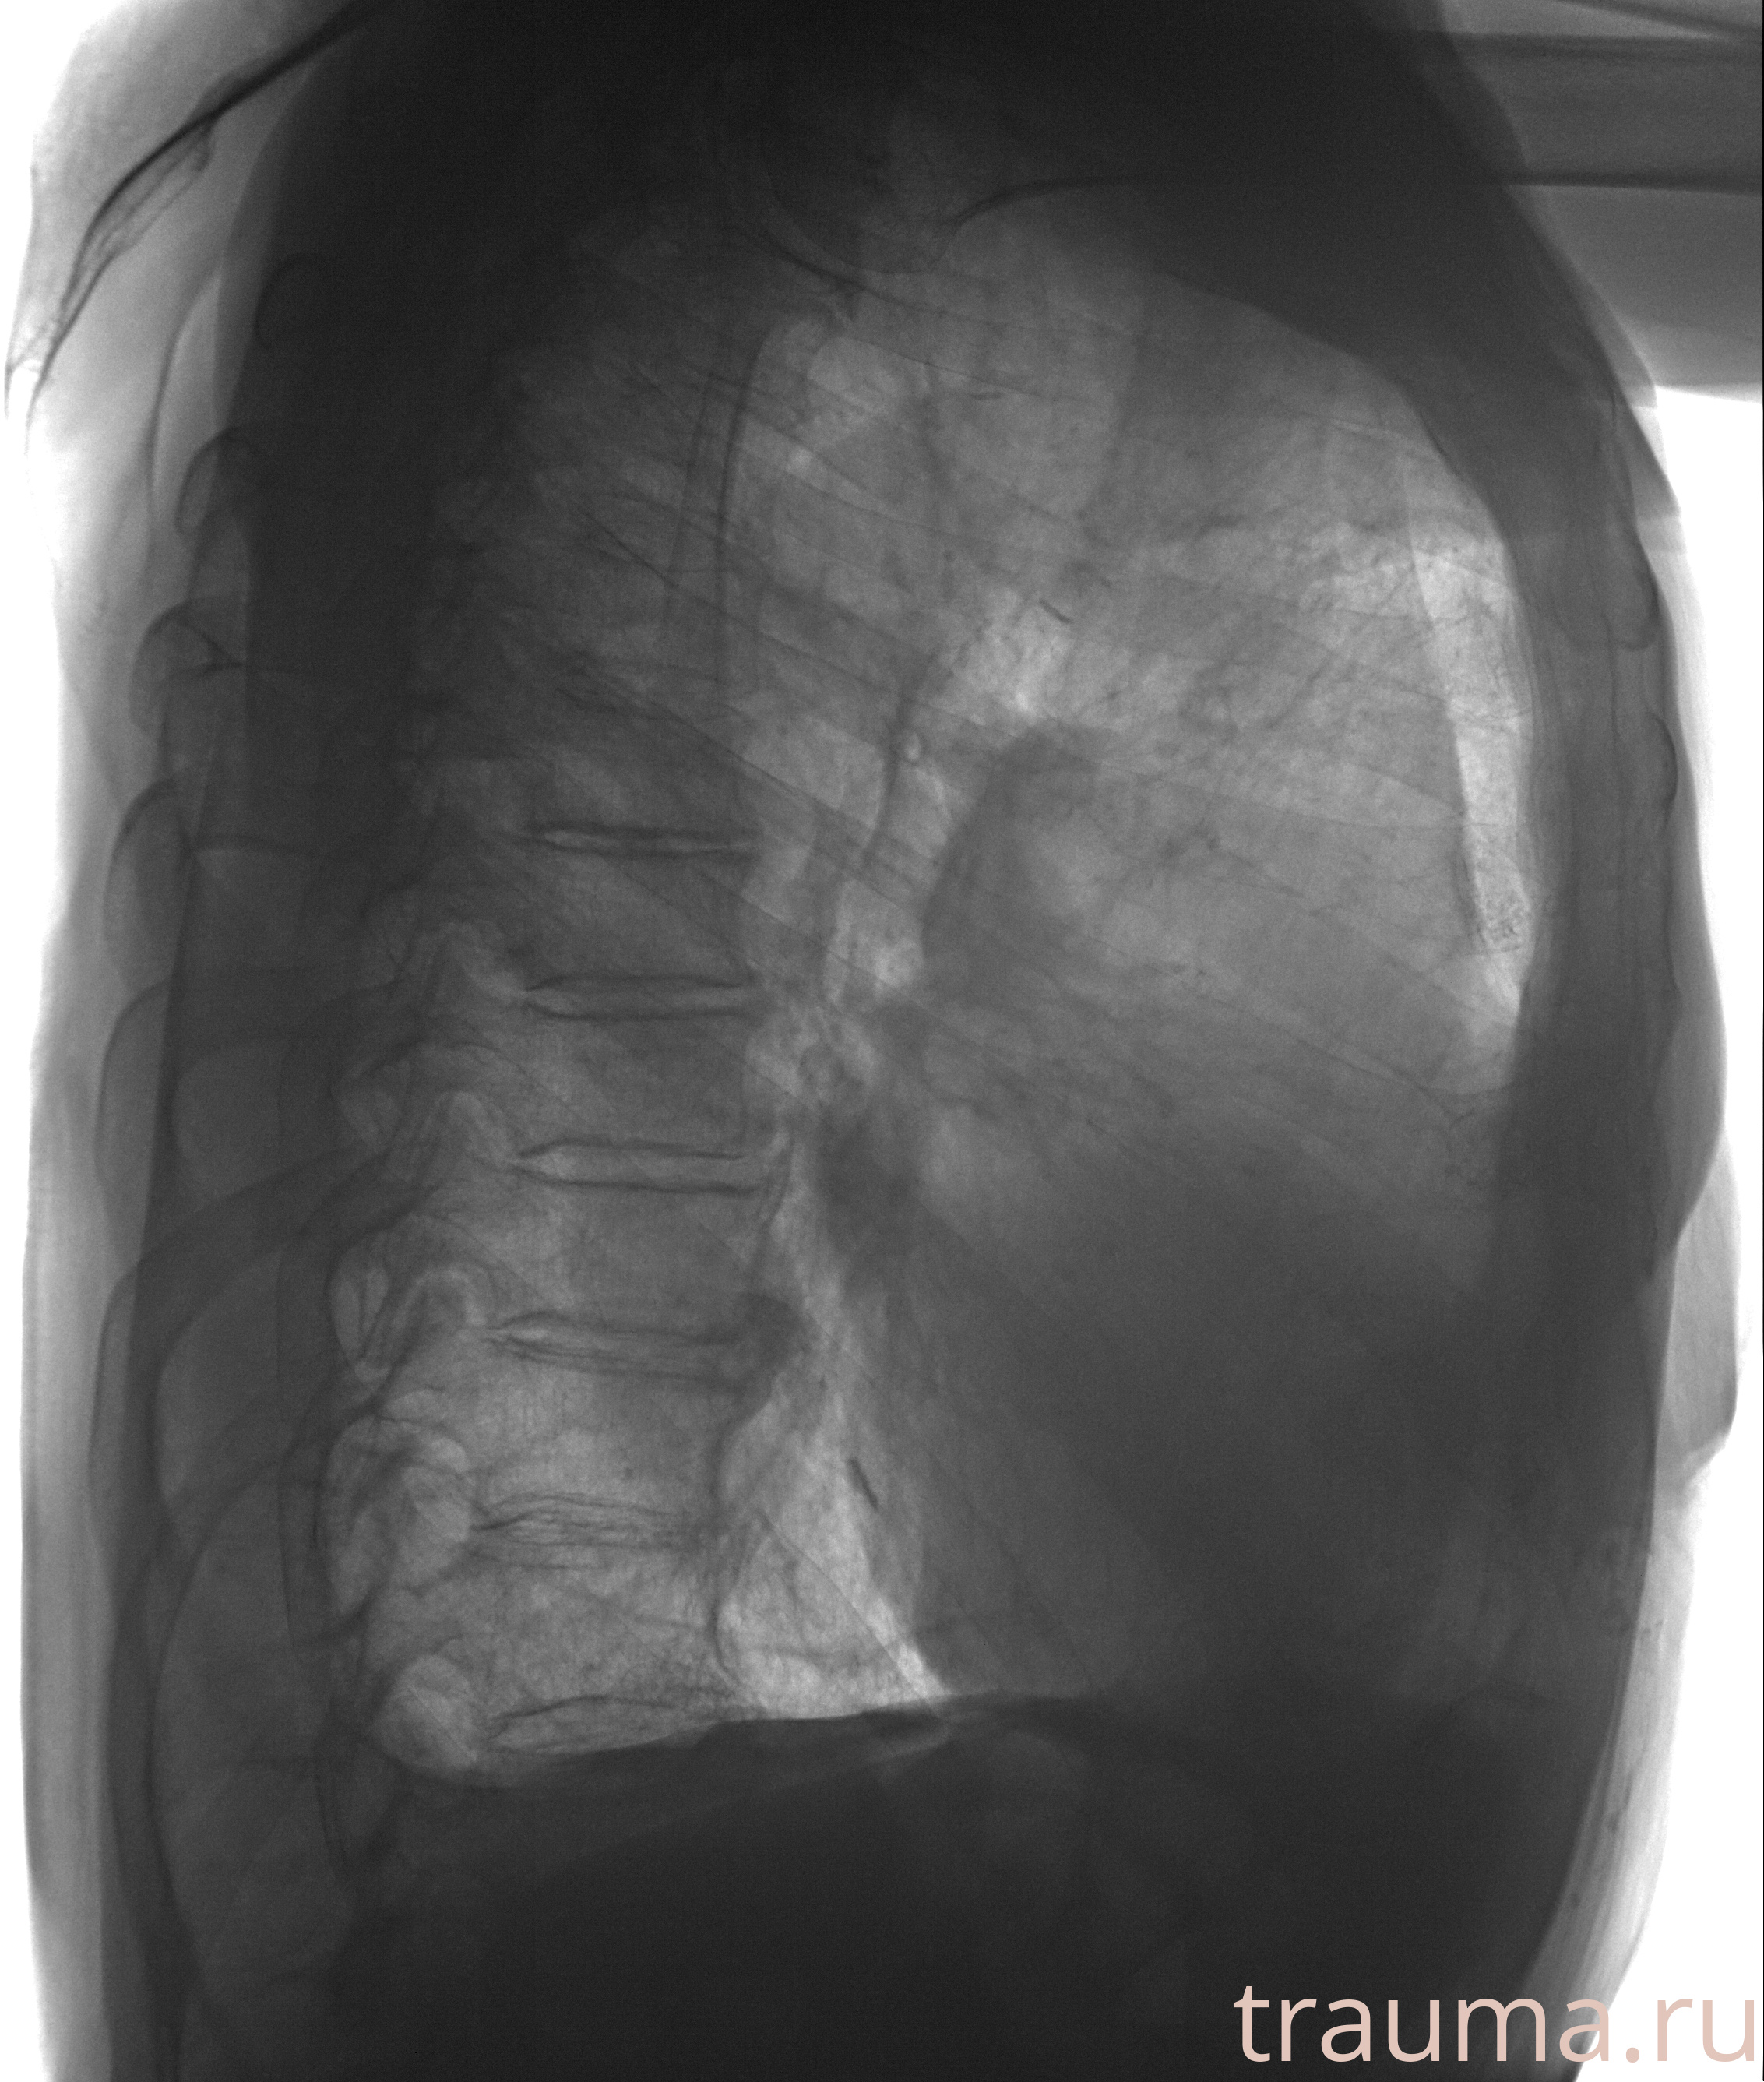

Рентген на дому: по вашему адресу приезжает врач-рентгенолог, травматолог-ортопед с мобильным рентгеновским аппаратом, проводит диагностику травмы или заболевания, делает необходимые рентгенограммы, дает рекомендации по дальнейшему лечению. Получить качественные снимки в домашних условиях возможно благодаря уникальной методике, разработанной МосРентген Центром для института  Склифосовского

при переломе шейки бедра и пневмонии от компании МосРентген Центр - партнера Института имени Склифосовского